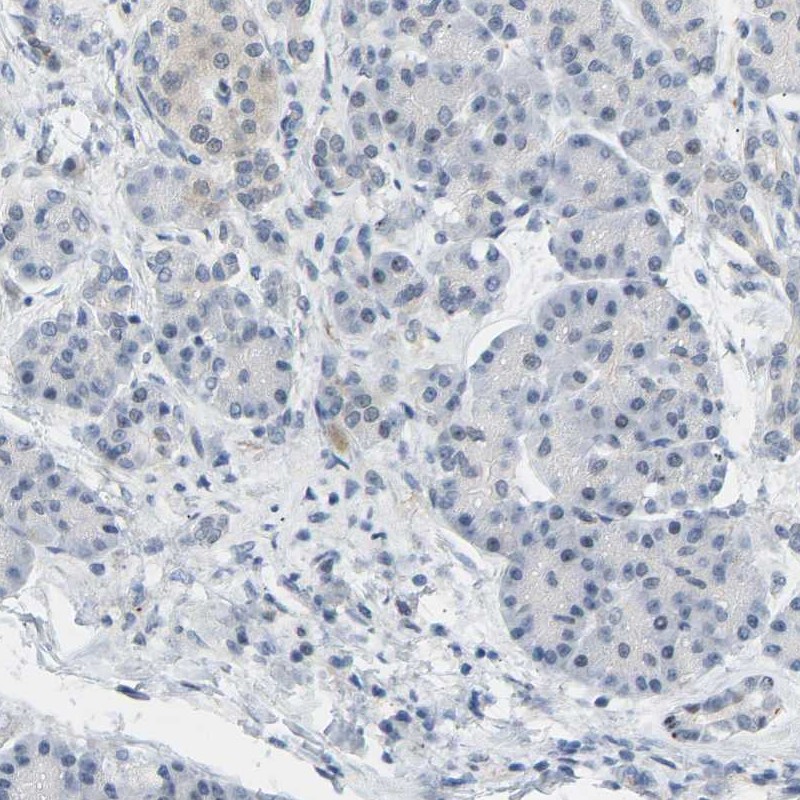

Immunohistochemistry analysis in human thyroid gland and pancreas tissues using Anti-BAG1 antibody. Corresponding BAG1 RNA-seq data are presented for the same tissues.